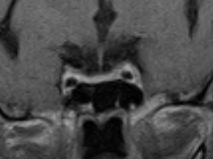

She was counselled for total resection of the tumour through an Endoscopic endonasal approach (EEA). EEA was performed through the right paraseptal route with the left rescue flap using the standard endoscope (Fig. 2). ICG was administered and a custom ICG-integrated endoscope was introduced. The tumour was visualized as appearing non-fluorescent compared with the normal pituitary gland (Fig. 3). The adjourning ICA was also visualized (Fig. 4). A soft whitish tumour was resected after capsulotomy. The anterior and posterior lobes were confirmed and remained fluorescent with ICG. Pseudo capsulectomy was added. After total resection, hemostasis was confirmed and the sellar floor was repaired.

Figure 3. Custom endoscopic view after ICG administration showing the less fluorescent adenoma (marked **) and the normal gland pushed to right (marked x).

Comment: This case highlights the advantages of using ICG assistance in the intraoperative localization and subsequent total resection of a functioning pituitary microadenoma via the EEA approach in a technologically advanced referral center in Japan, a high-income society. A complete tumour resection is required in achieving resolution of hypercortisolism. This ICG technology offers that assistance and precision needed intraoperatively to separate the tumour from the normal gland as well as preserve normal glandular functions.